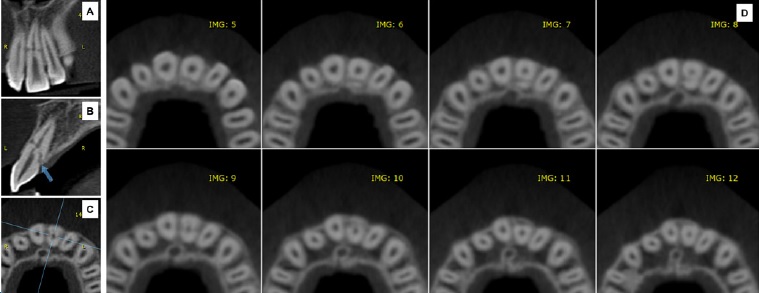

After 7 days, the patient was healing well without painful symptoms, fistula, tooth discoloration, or any radiographic aspect of pulp degeneration. Clinical and radiographic conditions remained satisfactory at the 4-week, 6-month, and 12-month follow-ups. Pulp vitality was confirmed by termal and percussion tests after 12 months (Figure 2A). Signs of repair between fractured segments were observed in the radiographic examination (Figure 2B). CBCT confirmed the diagnosis of oblique tooth root fracture and demonstrated hard tissue formation on the walls of the tooth root canal over the fracture line to unite the fractured segments (Figure 3 A-D).

Andreasen and Hjørting-Hansen12 described four prognostic possibilities for root fracture: healing with hard tissue, fibrous connective tissue, or both, or development of infectious granulation tissue. In our case, the fragments’ root canal anatomy remained unaltered, while a union of pieces with hard tissue was observed during the follow-up. Thus, we could predict healing based on the formation of reactionary dentin on the root canal walls over the fracture line associated with remodeling of the fracture periphery by reabsorption and new cementum.

CBCT scan significantly complemented the diagnosis of the case. According to Bourguignon et al.,4 the radiographic protocol requires at least one periapical radiograph, which can be very difficult depending on the child’s age and behavior. Still, the radiographic examination can be nonspecific. A study by Bornstein et al.5 showed the advantage of CBCT imaging over conventional imaging, pointing out that the first contributed to the diagnosis of 70% of root fractures. Furthermore, most root fractures diagnosed by CBCT were not submitted to endodontic treatment, suggesting that earlier diagnosis leads to lower rates of radical treatment.